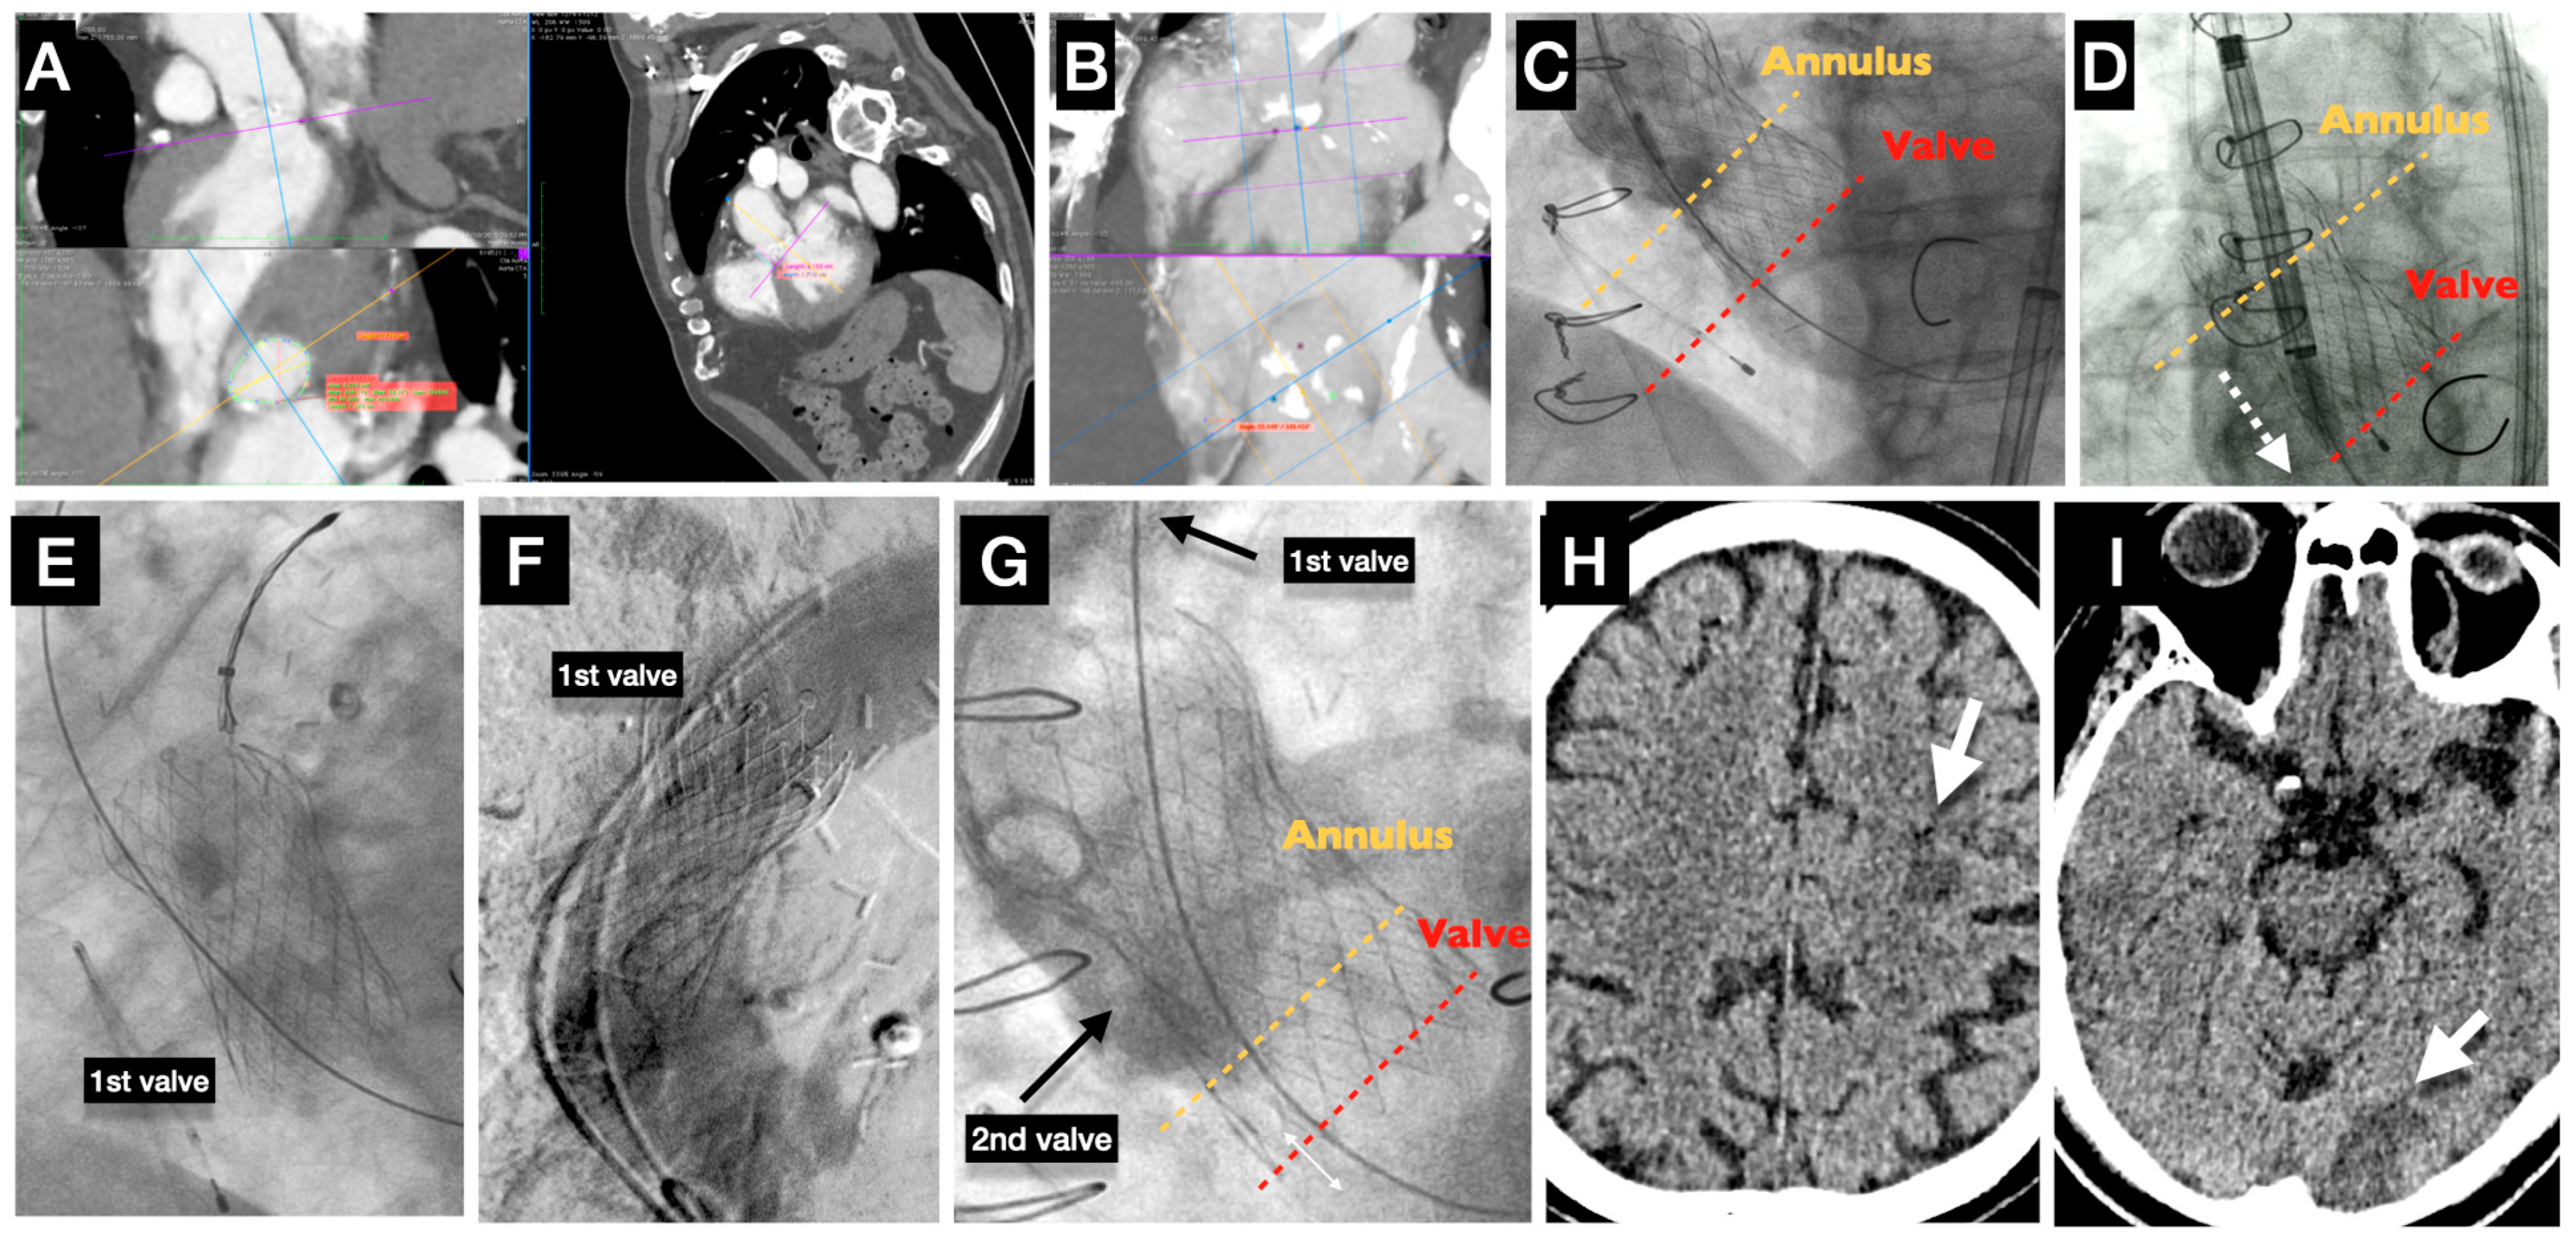

7. Acute Stroke (Case Example)